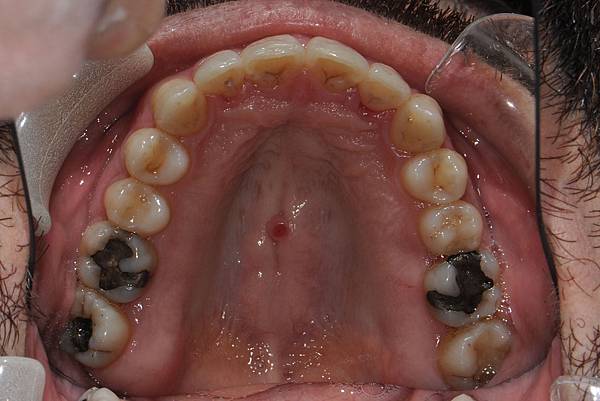

台灣的牙科醫療品質, 連外國人都說讚!此案例為深咬合併二級咬合 林醫師藉由正中上顎骨釘(HPPG technique)做上顎全齒列後移改善暴牙 讓本來五官就相當立體的艾先生,笑起來更燦爛了! 治療前/治療後-以上案例由林昇進醫師提供 分享到